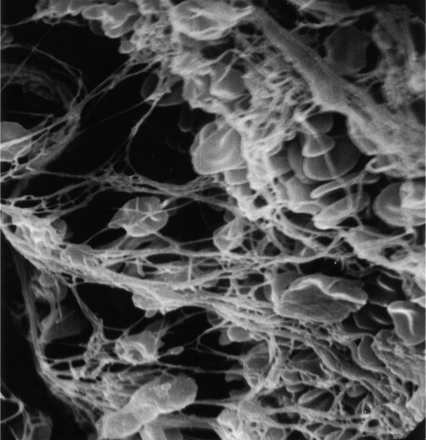

两个不同的结构模式与SEM可以认出:1)血栓展示先进成熟,所有的血栓性元素是如此密集集成单个实体没有清晰可辨的(图2),表明心脏稳定位置,持续暴露在剪切流;和2)血栓显示不同的纤维蛋白,红细胞被困,表明相对宽松的交联,一个活跃的地区特点的血栓仍在成熟的过程中,可能停滞的地区形成和再循环(图3)。这些模式被认为在不同比例在不同的患者。在某些情况下,可以联系具体的超微结构的研究结果推测病因的中风。值得注意的是这样一个广泛的血栓被恢复。

扫描电子显微镜图像3000×显示了一个紧密集成的血栓性组件的交联结构,即。,红色细胞、纤维蛋白和血小板,如此密集的个人实体不再明显,合并成一个坚固的结构。